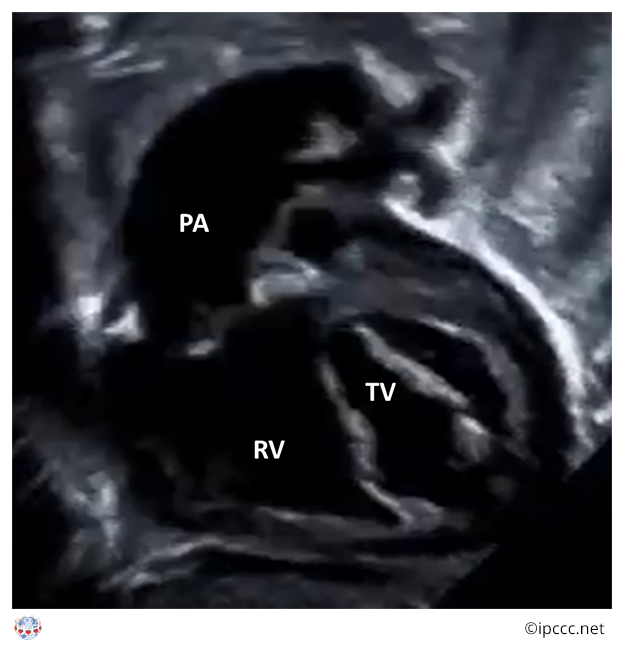

A spectrum of congenital cardiovascular malformations with normally aligned great arteries without a common atrioventricular junction, characterized by underdevelopment of the left heart with significant hypoplasia of the left ventricle including atresia, stenosis, or hypoplasia of the aortic or mitral valve, or both valves, and hypoplasia of the ascending aorta and aortic arch.

Echocardiogram